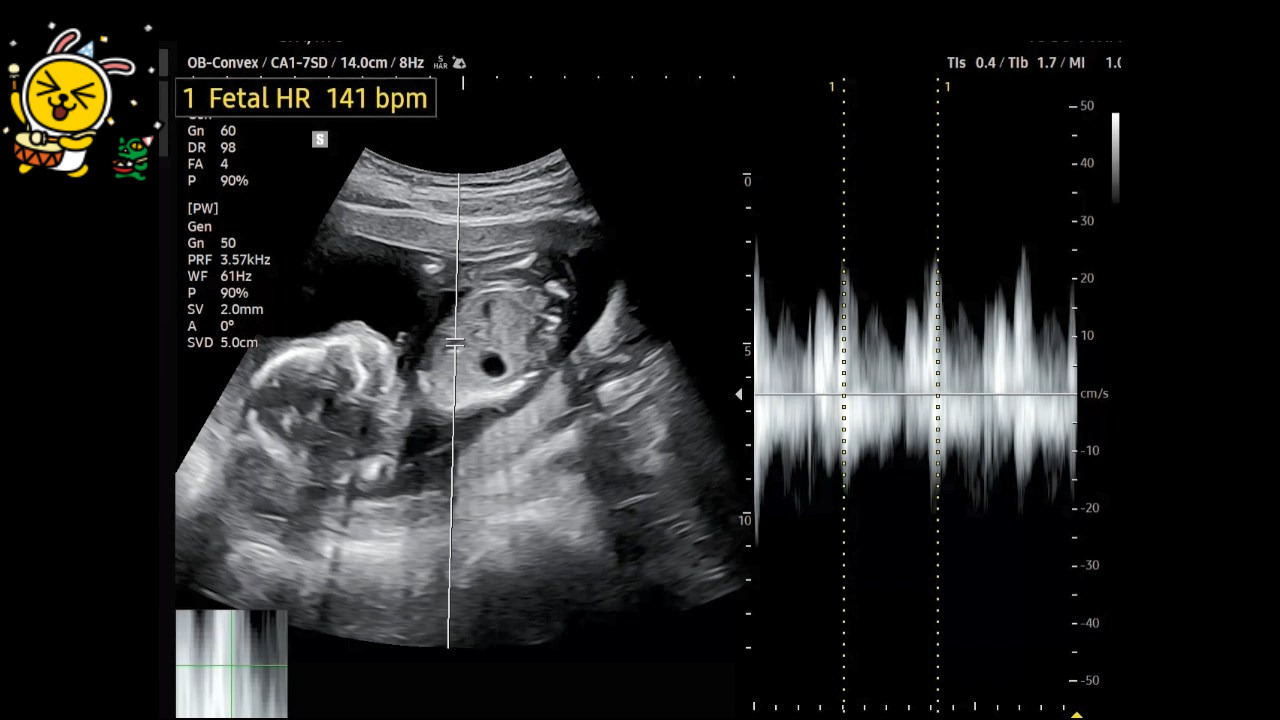

딸아이가 진찰을 받으면서 확인한 초음파 사진을 저에게 보내주었습니다.

초음파 사진은 4분이 넘는데 제가 알아볼 수 있는 항목만 캡처하여 보았습니다.

♬ FHR(Fetal Heart Rate)은 태아 심박수를 말하는데 '팡팡이'는 141 bpm입니다. 임신 17주~21주 평균이 148 bpm이라고 하니 정상적인 상태입니다.